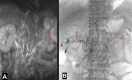

Purpose: Chyluria is a rare condition primarily prevalent in developing countries in tropical regions. In chyluria, there exists the communication between lymphatic vessels and the urinary tract, but the specific mechanism of this communication remains undocumented. The objective of this study was to assess the morphology of the main lymphatic vessels including the uro-lymphatic fistula, the thoracic duct using Magnetic Resonance Lymphangiography (MRL) and Intranodal Lymphangiography (IL).

Materials and methods: A retrospective study spanning five years, from January 2020 to January 2024, included 43 patients diagnosed with chyluria through cystoscopy and quantitative urine testing for triglycerides. These patients underwent MRL and then IL for uro-lymphatic fistula embolization.

Results: The study involved 43 patients with an average age of 66.1 ± 19.5 years, with a male-to-female ratio of 1:2. Uro-lymphatic fistula occurred predominantly in the left kidney (72.1%), followed by the right kidney (20.9%), and both sides (7%). MRL imaging showed the thoracic duct in 100% of cases but visualized only 84.5% of the uro-lymphatic fistulas. In contrast, IL imaging showed the thoracic duct in 51.5% of patients but visualized uro-lymphatic fistulas in 100% of cases. In the procedure of IL, the average visualization time of the thoracic duct was 45 minutes, with a range of 35 to 69 minutes.

Conclusion: MRL and IL complement each other in diagnosing the main lymphatic vessels in chyluria patients. The observed circulatory stasis in the thoracic duct supports the hypothesis that it contributes to increased pressure in the thoracic duct and the formation uro-lymphatic fistula as collateral circulations.